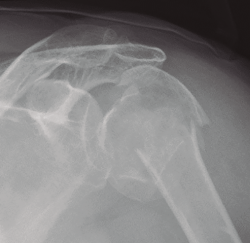

El examen radiológico debe consistir en radiologías simples de la clavícula y el hombro (Figura 2); también es recomendable una tomografía axial computarizada (TAC).

Figura 2. Radiografía simple de una fractura de clavícula en el tercio medio.